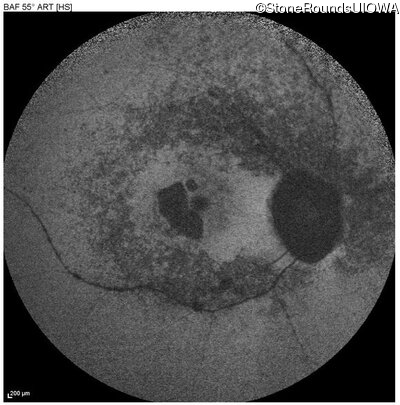

Age at visit: 63 years

OD OS

This 63 year old woman has had normal vision for most of her life, but recently developed difficulty seeing in dim light.

Diagnosis & molecular findings

Disease Gene Allele 1 variant(s) Allele 2 variant(s) Inheritance mode

AD Retinitis Pigmentosa SAG Cys147Phe TGT>TTT   AD